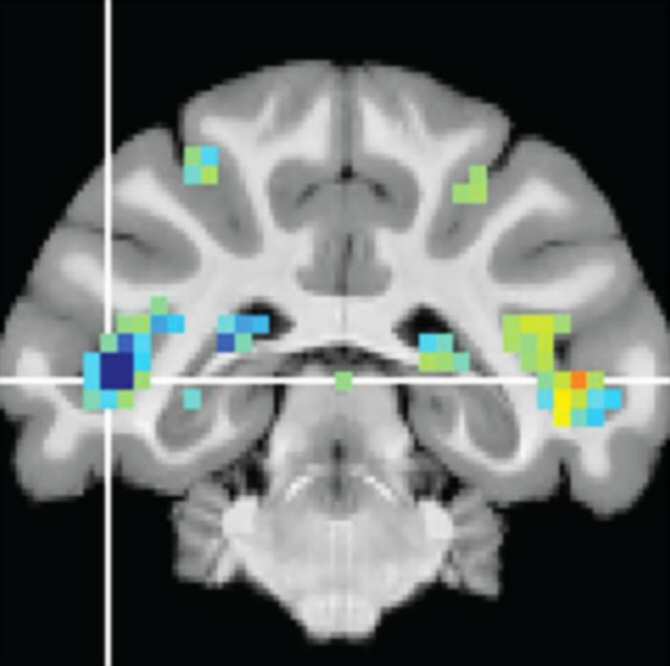

Un escaneo cerebral mediante una técnica especial de resonancia magnética revela cambios de actividad en el surco temporal superior. (Imagen: Richard Krauzlis, National Eye Institute)

Para estudiar la atención visual, los investigadores trabajan con monos entrenados para realizar tareas específicas de atención visual. Mientras fijan sus ojos en un punto que está al frente, los monos prestan atención o ignoran específicamente los eventos que suceden en la periferia visual, en este caso un conjunto de puntos en movimiento que cambia de dirección, ya sea en el lado derecho o en el lado izquierdo de su campo visual. El colículo superior se activa fuertemente cuando los monos prestan atención al evento visual, y menos cuando no le dedican atención. (Fuente: NCYT de Amazings)